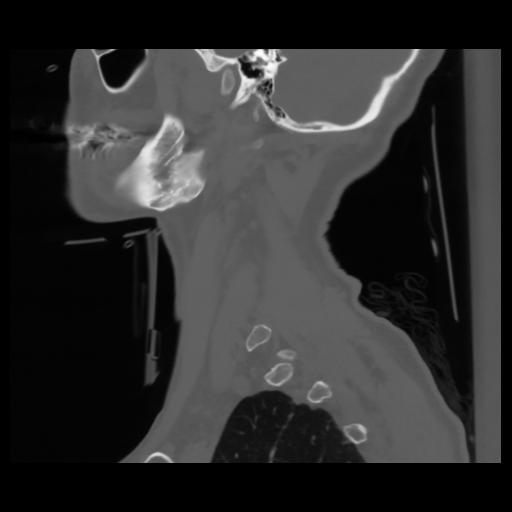

14 P.BLANDAS,,Sagittal,2.000,P.BLANDAS,Sagittal,